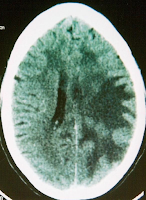

CT scan of the head revealed white matter edema of the left parieto-occipital region with mass effect on the left ventricle with midline shift suggestive of venous thrombosis. Contrast CT of the

head showed enhancement of these lesions suggestive of demyelination

| Fig 1 Contrast enhanced CT scan showing mass effect and enhancement in Parietal lobes |